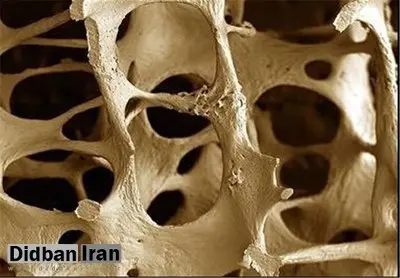

به گزارش پایگاه خبری تحلیلی دیده بان ایران، در بیماری پوکی استخوان، استخوانها ضعیف و شکننده میشوند. بیش از ۴۴ میلیون امریکایی دچار این بیماریاند و رد پای این بیماری سالانه در حدود ۲ میلیون از شکستگیها دیده میشود. علاوه بر این پزشکان گزارش دادهاند که زنان بیشتر از مردان دچار شکستگی استخوان ناشی از این بیماری میشوند. با این حال، گویا مرگ ومیر ناشی از آن، مردان را بیش از زنان درگیر میکند.

دکتر «آلن ژانگ»، نویسنده یک تحقیق تازه در این زمینه گفت: «اگرچه در مقایسه با مردان، زنان بیشتر دچار شکستگیهای ناشی از پوکی استخوان میشوند اما آسیب آن مردها را بیشتر از زنان در معرض خطر مرگ و میر قرار میدهد».

مطالعه مشخص کرد که میزان مرگ و میر پس از یک سال از رخداد شکستگی تقریباً ۱۹ درصد برای مردان و ۱۳ درصد برای زنان ثبت شده بود. شکستگی مچ پا تنها استثنائی بود که هم در مردان و هم در زنان، مقدار مشابهی را (در حدود کمی بیشتر از ۸ درصد) نشان میداد.

بر اساس یافتههای این تحقیق، زنان ۵ برابر بیشتر از مردان احتمال دارد دچار شکستگی اولیه ناشی از پوکی استخوان شوند اما هنوز احتمال پایینی از خطر شکستگی بعدی، ۳ سال پس از شکستگی اول برای آنها وجود داشت. مردانی که برای درمان شکستگی اولیه نیاز به جراحی پیدا کرده بودند، بر عکس زنان با احتمال بالایی از خطر شکستگی بعدی، ۳ سال پس از شکستگی اول رویارو بودند.

این تحقیقات همچنین نشان داده است که فقط یک استثنا در این زمنه وجود داشته و آن هم احتمال مساوی شکستگیهای حاصل از فشار ستون فقرات در هر دوی زنان و مردان مبتلا به پوکی استخوان بوده است.